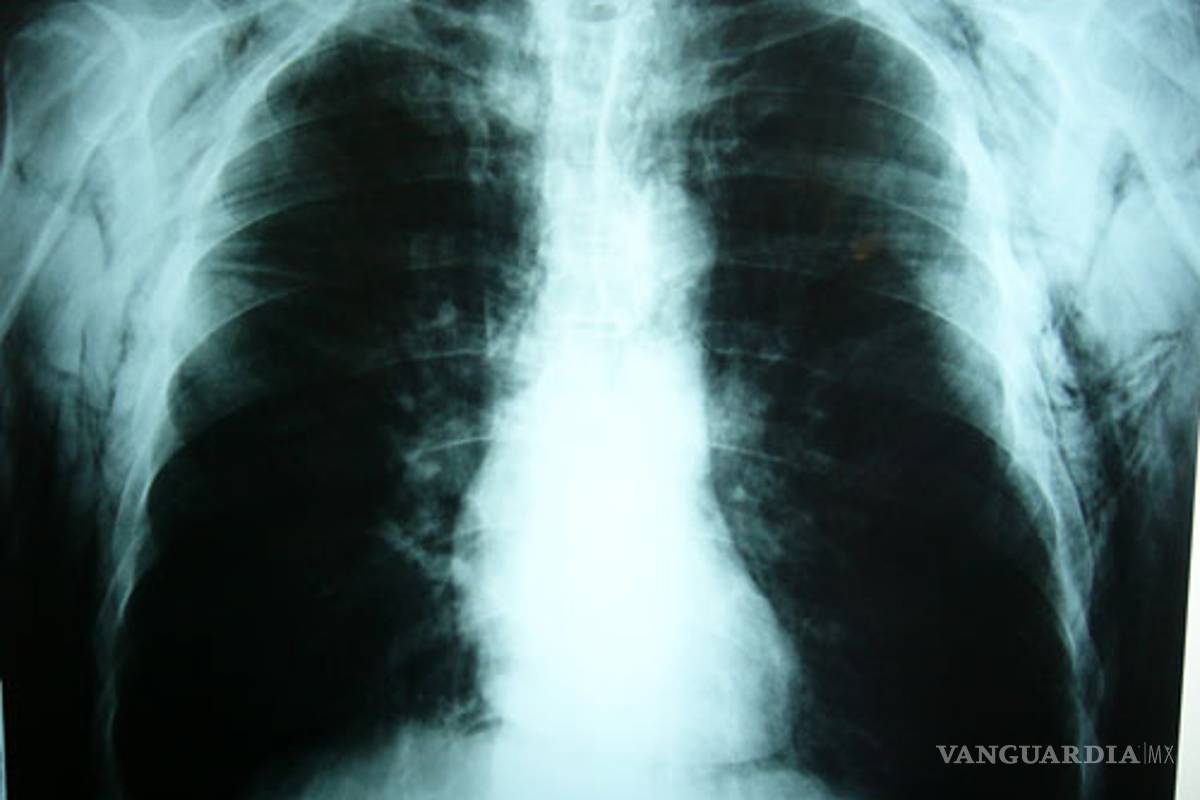

Los pulmones de pacientes que usaban aparatos para facilitar su respiración se regeneraron tras ser tratados con células madre extraídas de su médula ósea

Los pulmones de tres de los cuatro pacientes se regeneraron tras ser tratados con células madre extraídas de la médula ósea de los propios voluntarios. Esos tres pacientes ahora andan sin la necesidad de aparatos para facilitar su respiración.

Las células tronco fueron inyectadas en la corriente sanguínea de los voluntarios de forma que se alojaran en la región pulmonar. Estas células redujeron los espacios entre las paredes que forman el tejido donde el oxígeno es aprovechado por el cuerpo. El enfisema se caracteriza precisamente por las grandes cavidades que quedan en el tejido y que dificultan la respiración.